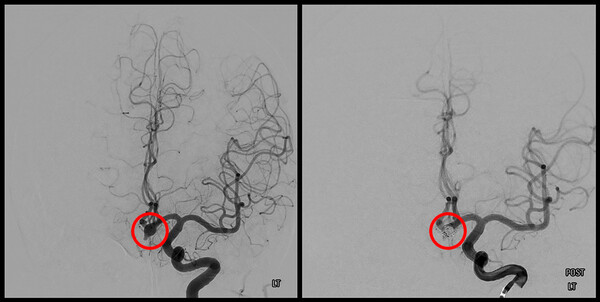

치료방법은 뇌동맥류의 크기, 모양, 위치 및 환자의 상태를 고려해 선택하게 된다. 머리를 열고 수술하는 개두술, 클립 결찰술, 뇌혈관 내부로 접근하는 코일 색전술이 있다. 각 방법에 장단점은 있지만, 치료의 수준이 계속 발전하고 있어 높은 완치율을 보이고 있다. 최근엔 미용까지 고려해서 수술할 정도로 안전하게 치료를 하고 있다. 따라서 전문가의 의견에 따라 환자별 맞는 치료법으로 신속하게 치료하는 것이 중요하다.